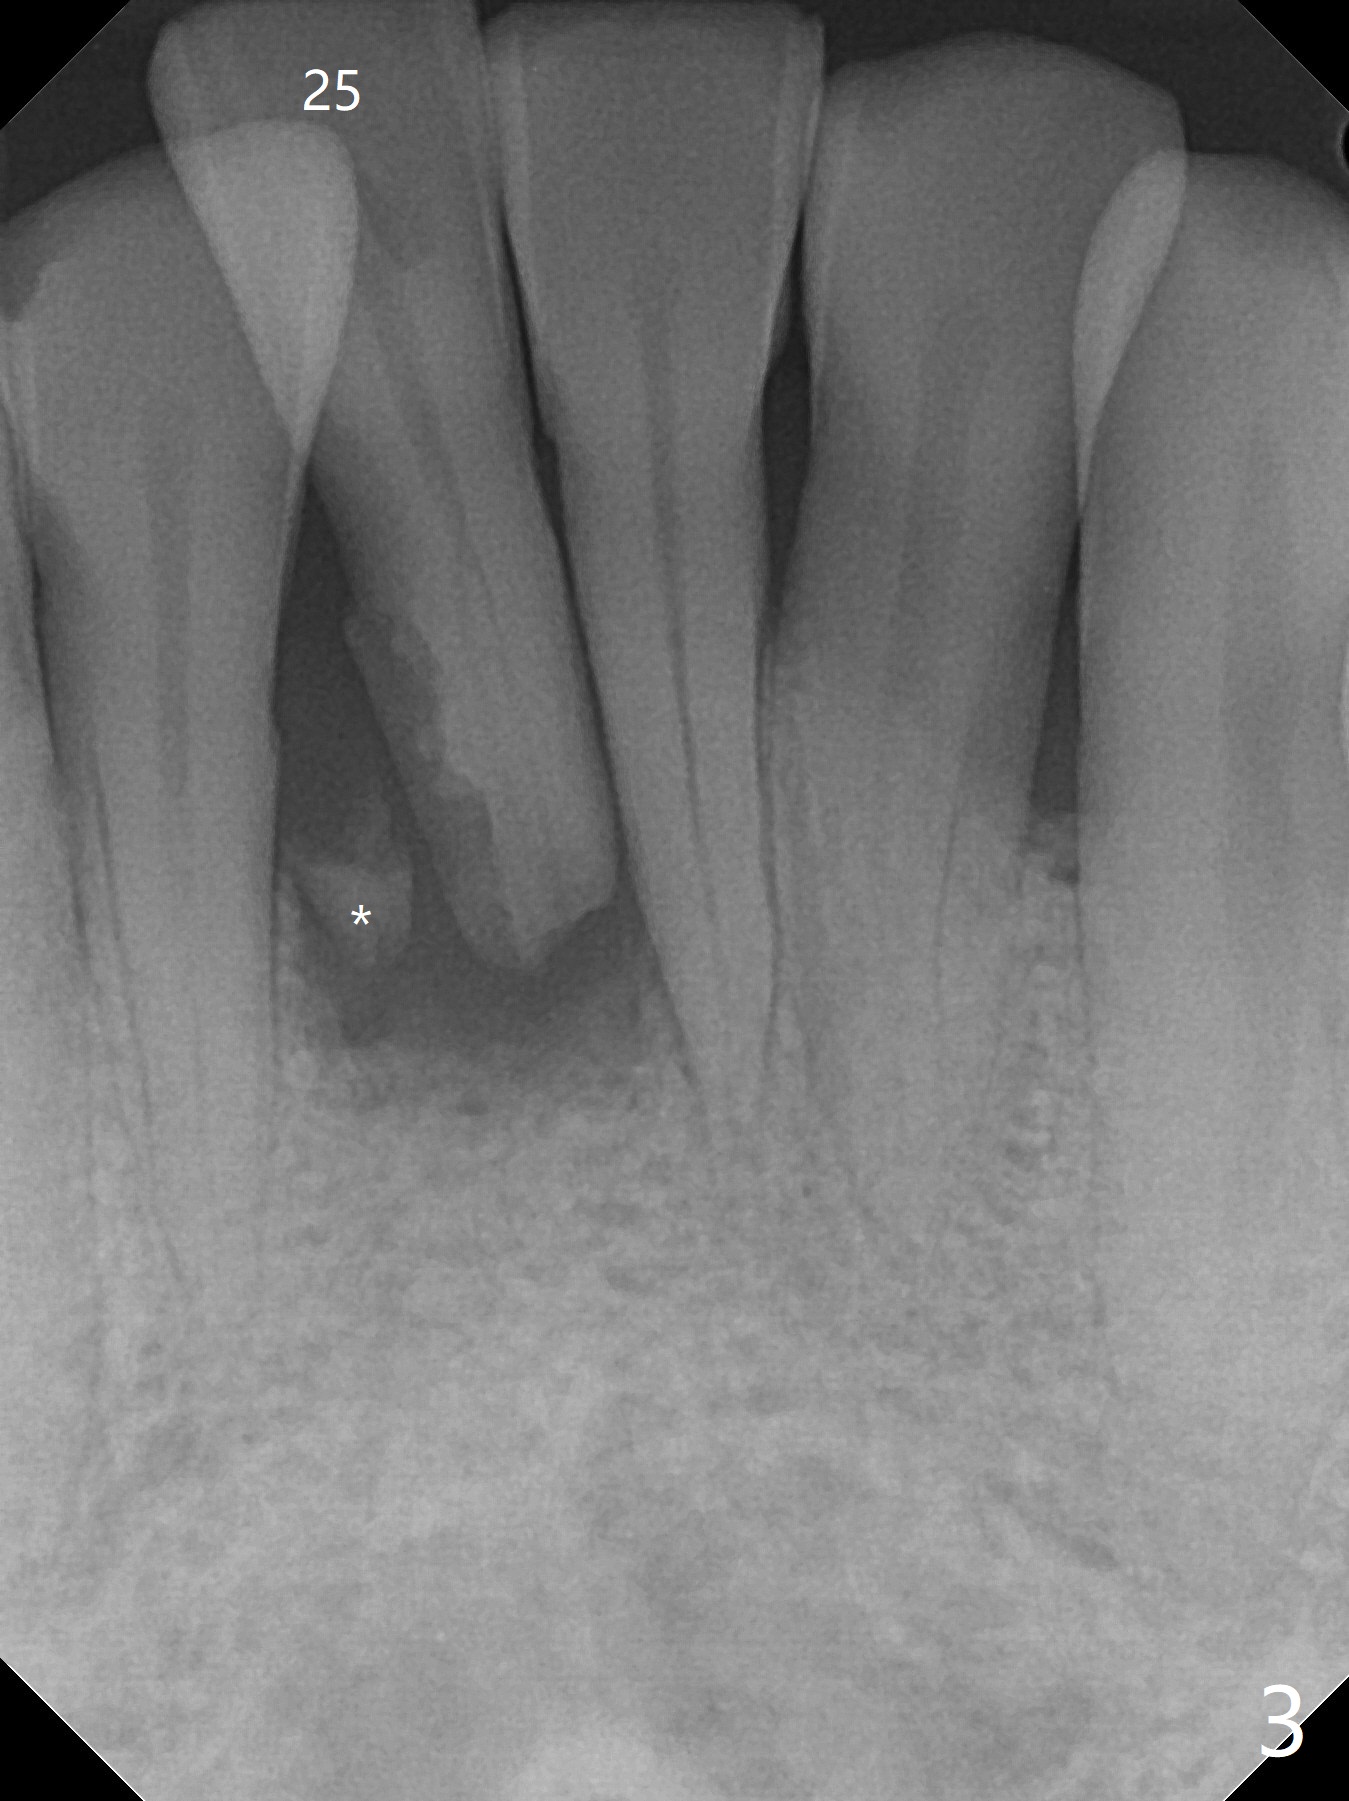

A 47-year-old man, a possible bruxer (Fig.1), is concerned about the mobile 2nd molar and lower central incisor (Fig.2,3). To prevent periimplantitis, a 2 mm 1-piece implant and a short one (5x5 mm) will be placed subcrestal at these sites, respectively (Fig.4,5). Sticky bone is a must. Pulpal test will determine whether RCT is required for #30 (Fig.5 curved white line). In fact the tooth #30 is tested to be vital. Onlay graft is an option for #31 (Fig.6 red rectangle). There is history of #32 extraction. The severely periodontally affected tooth #25 (Fig.7 *) has narrow mesiodistal space (Fig.8). It is the best treated with extraction with bone graft and self drifting.